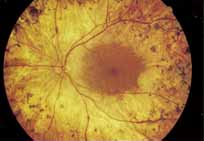

Although there is no reported genetic heterogeneity, there is wide phenotypic variation within the disorder. The major finding within the macula is a classic radial cystic maculopathy. Although retinal signs have been described in infants as young as 3 months, foveal schisis may be difficult to detect, leading to underdiagnosis. The diagnosis is usually not made until the affected male reaches school age (4 to 8 years of age) and encounters visual problems secondary to foveal involvement. Typical foveal schisis findings have been reported in 68% to 100% of eyes within various series.37,38 Foveal schisis is the only finding in about half the cases. It is characterized by the presence of radiate perifoveal microcysts located in the nerve fiber layer (Fig. 1) with radiate plications of the overlying internal limiting membrane that are seen especially well on monochromatic (red-free) photography (Fig. 2). The microcystoid change may slowly progress to form a macular cyst or hole. Foveal schisis has been reported in association with Goldmann-Favre vitreotapetoretinal dystrophy and rarely may be seen in rod-cone dystrophy or as an autosomal dominant or recessive condition.39–43